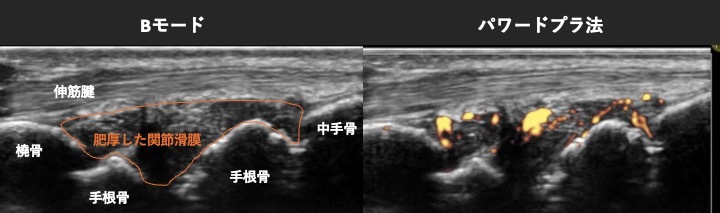

関節リウマチの診療では、関節エコー(超音波検査)が大変重要な役割を担います。この関節エコーが、早期診断の鍵となるケースが多くあります。

超音波を使って関節内の滑膜、腱、靱帯、骨、軟骨などをリアルタイムで可視化できるうえに、痛みもほとんどなく、患者さんの負担が少ない検査方法だからです。特に、関節リウマチの診断に欠かせない滑膜肥厚や血流増加を評価するうえで非常に有効であり、診断の精度を高めます。

関節リウマチのエコー所見

大きなポイントとして、微細な滑膜炎を捉えやすいことが挙げられます。目立った腫れや血液検査での異常が見られなくても、関節エコーなら炎症を早期に発見できます。これによって、早期診断と治療開始が可能となり、関節の破壊を未然に防ぐことにつながります。また、関節リウマチに似たほかの病気との鑑別にも役立つため、医師がより的確に治療方針を立てるうえで貴重な手段です。